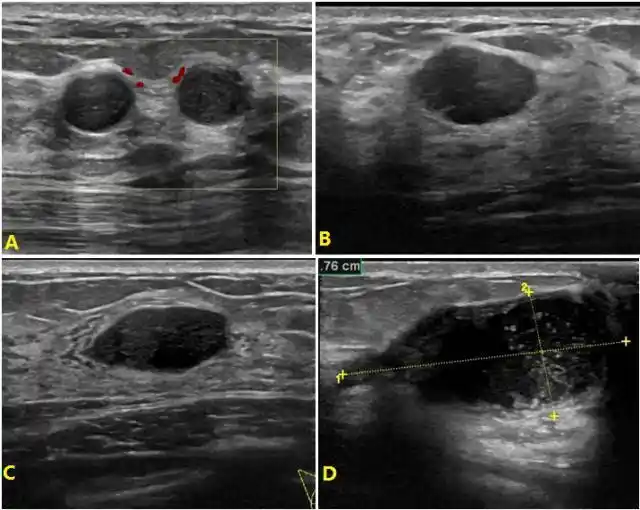

3步搞定乳腺常见病超声表现

书摘笔记——乳腺超声检查的难点与误区